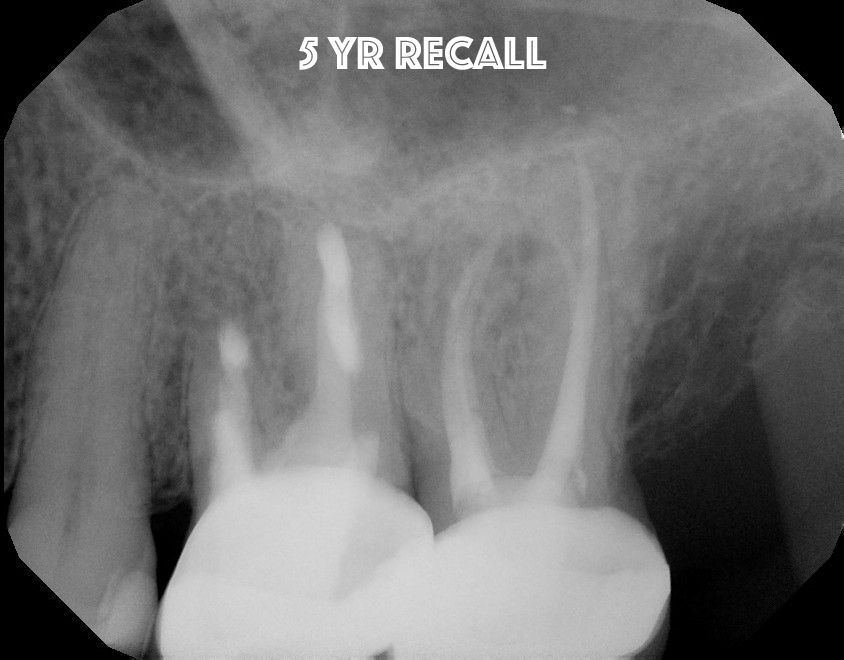

Tooth #14 was carefully extracted and all 3 canals were resected, retrofilled and reimplanted within minutes.

5 Year recall shows great apical bone healing.  The tooth is functional, normal percussion, normal probing.  Intentional implantation should be considered as an opion in certain situations.